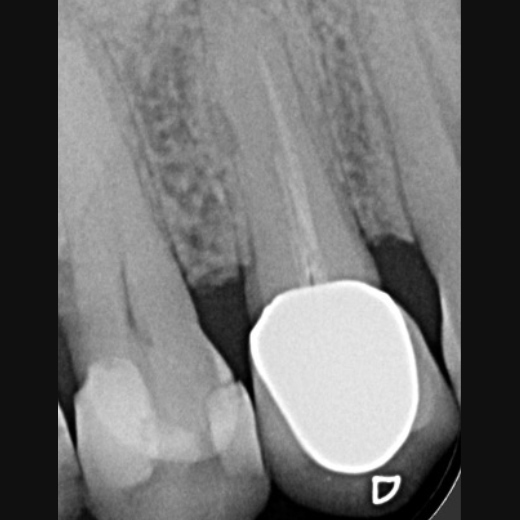

Fallbeispiel: Revision 46 (und 45) Recall 6 Monate

Bringt eine Wurzelkanalbehandlung nicht den gewünschten Erfolg, bedeutet dies nicht, dass ein Zahn nicht mehr zu erhalten ist. Mit einer Revisionsbehandlung können auch bereits wurzelkanalbehandelte Zähne langfristig erhalten werden!